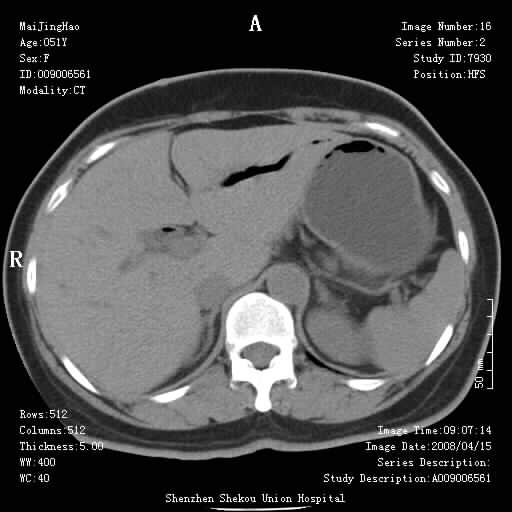

以下是引用余辉在2008-4-26 8:55:00的发言:[br]患者有结石史,此次腹痛4小时,胆总管全程扩张,应有胆总管末端梗阻,此次仍考虑胆结石症,积气不外两种原因,一种是结石下移时肠道内气体逸入,其次为产气菌感染。(倒数第三幅图像于扩张之胆总管末端似可见稍高密度影,考虑为结石影)

以下是引用yangyudong333在2008-4-26 6:17:00的发言:[br]1胆系感染,可能为金葡菌感染,2考虑有化脓性胆管炎致胆总管扩张,3胰头部增大,建议做增强

以下是引用听蝉观竹在2008-4-26 11:41:00的发言:[br]胆道手术分两种情况:[br]1、如果仅仅做胆囊切除手术,肝内胆管不会积气,只会出现胆总管代偿扩张,因为奥迪氏括约肌依然功能正常胆道与外界并不相通;[br][br]2、胆囊切除+胆总管空肠吻合手术(即roux-y式),则肝内胆管会出现积气,只是因为胆管与小肠相通,气体来源于小肠。这是临床十分常见的手术。[br][br]这个病例应该是胆囊切除+胆总管空肠吻合手术,是正常手术后表现,并不是胆道感染的表现。

以下是引用听蝉观竹在2008-4-27 10:10:00的发言:[br]关于胰头大小问题有几种测量方法和正常值:[br][br]1、直量法:横径<4cm;[br]2、胰头横径与相邻层面椎体横径的比值为二分之一,超过椎体横径就提示胰头增大;[br]3、正常组成年人肠系膜上动、静脉水平夹角正常值范围为4.9°~34.7°大于35°提示胰头增大。[br][br]上述方法只是一种具体的判断,是“量”的评估,更重要的是“质”的评估:一是观察边缘是否光滑,有无局部隆起,有无分叶;二是观察密度(增强,尤其在动脉期和门脉期)是否均匀。[br][br]所以对于胰头是否有异常不仅仅是是目测可以解决问题的,不要轻易就说“胰头增大”。还有一个问题就是测量胰头应该在增强ct上进行,这样可以避免将血管测量进去。[br][br]为什么啰嗦讲怎么多,因为我们实际工作中同样存在影像科医生和临床医生动不动就说胰头增大,说是胰头癌。大家看看是不是这种情况?[br][br] 我个人观点-----本病例的胰头不增大。[br][br][本贴已被 听蝉观竹 于 2008-4-27 10:12:41 修改过]